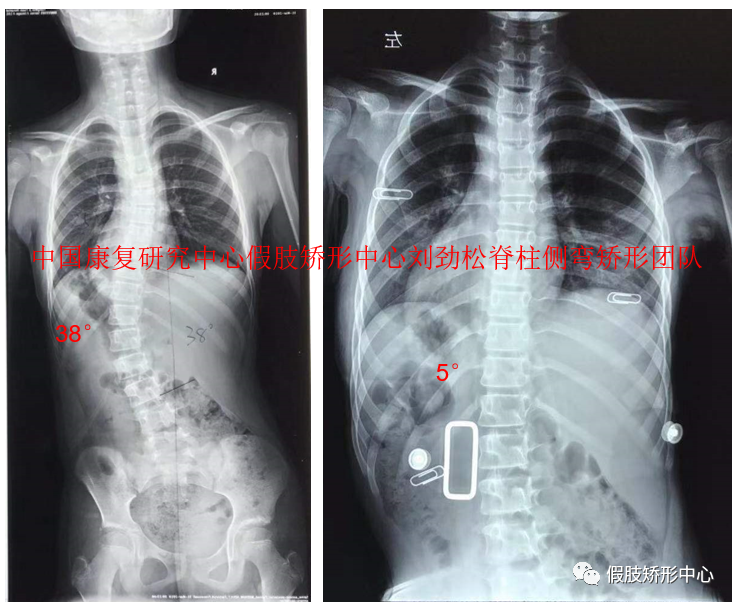

2019年假肢矯形中心舉辦索本海姆SCS脊柱側彎矯形器培訓班,得到學員的一致好評。近兩年利用3D數字化技術完成SCS脊柱側彎矯形器近千例,效果良好。

SCS脊柱側彎矯形器個案

SCS脊柱側彎矯形器3D雕刻